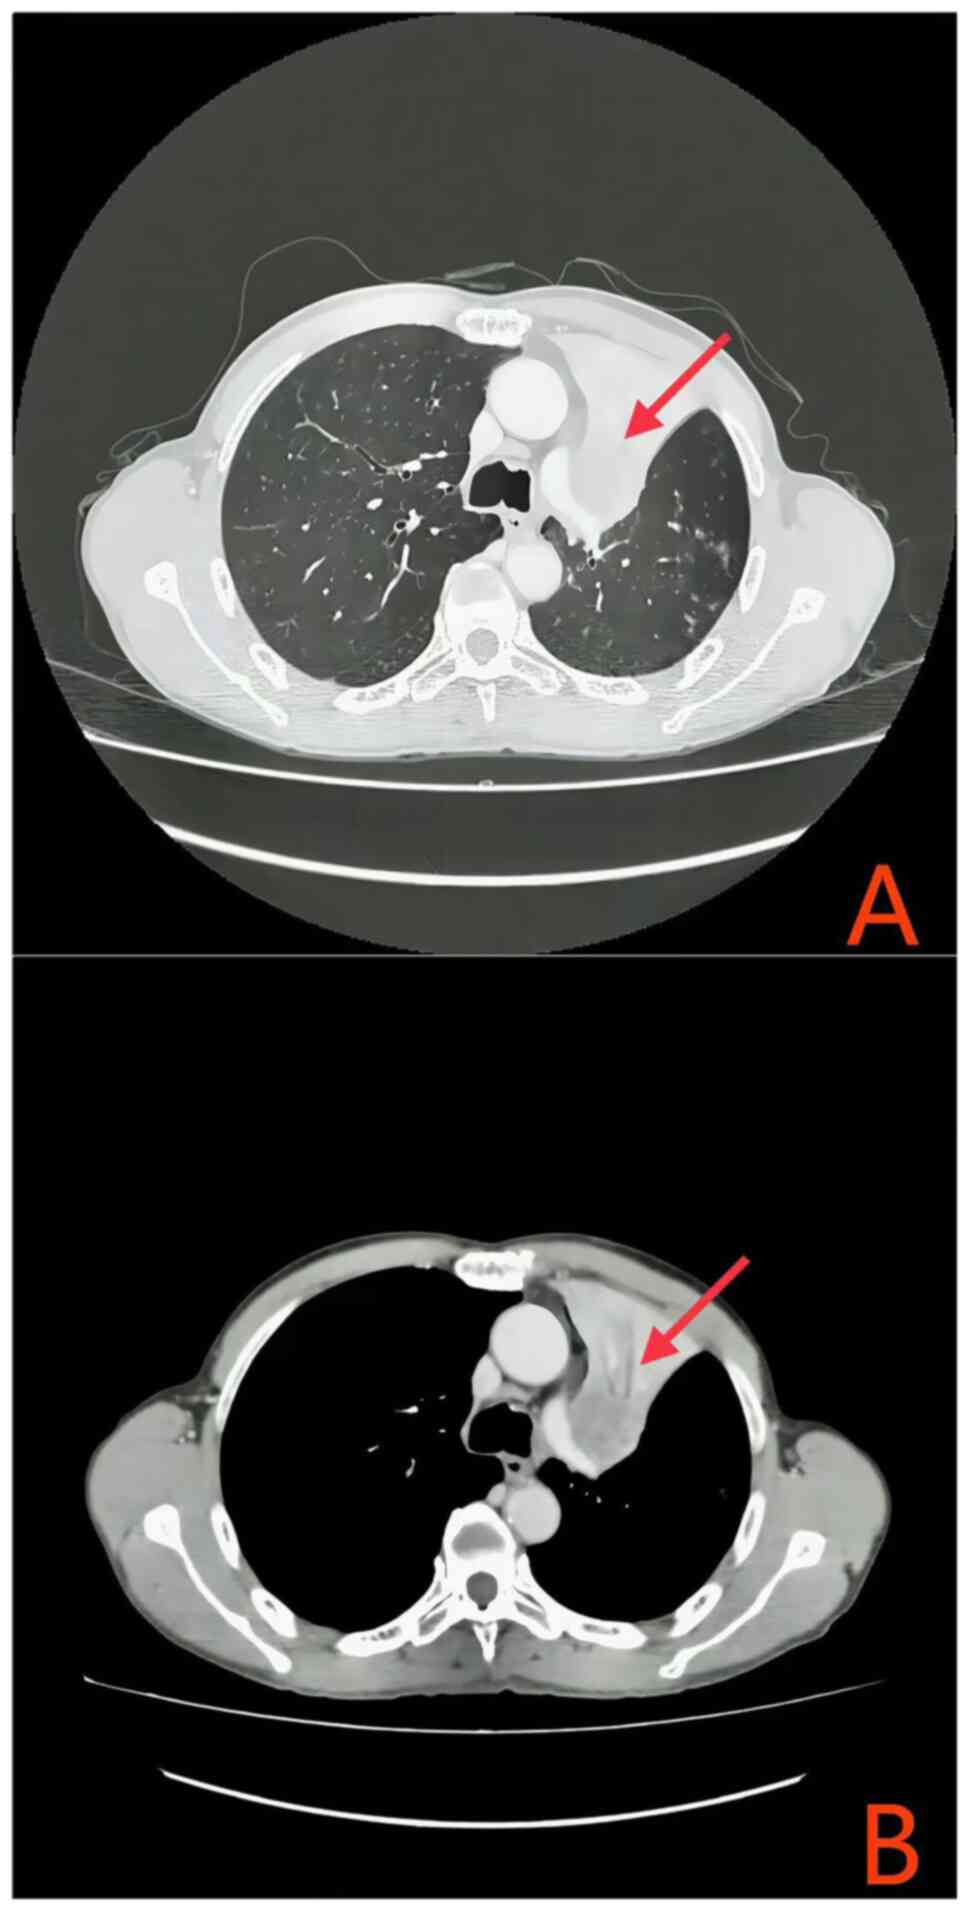

In July 2023, the patient began treatment with a combination of albumin-bound paclitaxel, cisplatin and a PD-1 inhibitor. Tislelizumab 200 mg was administered via intravenous drip on Day 1. Paclitaxel (albumin-bound) 395 mg was administered via intravenous drip on Day 2. Cisplatin 110 mg was administered via intravenous drip from Day 2 to Day 3, divided into two administrations. The treatment cycle is 21 days, and this is the first cycle. Subsequently, in August 2023, a comprehensive re-evaluation of the hepatic and renal function of the patient, along with electrolyte profiling, revealed hyperkalemia, hyperphosphatemia, hyperuricemia, hypocalcemia and signs of acute renal impairment (Table I); however, the patient remained asymptomatic for arrhythmia, tetany, muscular spasms, hypotension, nausea, vomiting, abdominal discomfort or oliguria. Based on consensus guidelines from the TLS expert panel (9), a diagnosis of laboratory-confirmed TLS was considered. Treatment included rectal administration of Shenkang Shuan (4 g (4× daily), oral Niuduqing granules 5 g for kidney protection (3× daily) Until renal function returns to normal, oral cyclosilicate sodium powder to reduce potassium levels (3× times daily, adjusted to 5 g orally 3× daily to maintain stability once the blood potassium levels normalized), and febuxostat 20 mg (once daily) to decrease uric acid levels. Fluid replacement and dynamic monitoring of liver, kidney and heart function were initiated, along with symptomatic treatment [Administer intravenous infusion of 0.9% sodium chloride injection at a dosage of 3 l/m2 daily, and maintain urine output at a rate greater than 100 ml/(m2•h)]. After fluid replacement, urine alkalinization, electrolyte correction and kidney protection, the parameters of the patient improved (Table I). In accordance with the monitoring recommendations outlined in the National Comprehensive Cancer Network® guidelines during initial therapy (10), due to the manifestation of TLS symptoms in the patient, a timely assessment of any changes in the condition of the patient was imperative. Therefore, following a single cycle of chemotherapy combined with PD-1 immunotherapy, radiological reassessment performed at 4 weeks post-treatment demonstrated a marked decrease in the size of both the primary lung lesion and the metastatic lymph nodes when compared with the baseline prior to treatment (Fig. 3). The treatment efficacy was classified as a partial response (PR) based on the Response Evaluation Criteria in Solid Tumours (RECIST) 1.1 criteria (11) (Figs. 2 and 3). From the second cycle onwards, the chemotherapy drug was adjusted to albumin-bound paclitaxel + carboplatin (Tislelizumab 200 mg was administered via intravenous drip on Day 1. Paclitaxel (albumin-bound) 395 mg was administered via intravenous drip on Day 2. Carboplatin 440 mg was administered via intravenous drip on Day 2. The treatment cycle is 21 days). Upon completion of the systematic treatment, the efficacy evaluation according to RECIST 1.1 criteria was classified as a PR (Fig. 4). As of April 2024, the patient's condition remains stable.

Figure 3.

After one cycle of programmed death-ligand 1 inhibitor therapy combined with chemotherapy. Chest contrast-enhanced CT: (A) The primary tumor has exhibited a substantial reduction in size, accompanied by the resolution of atelectasis. (B) Metastatic lymph nodes in the drainage region have undergone a diminution.